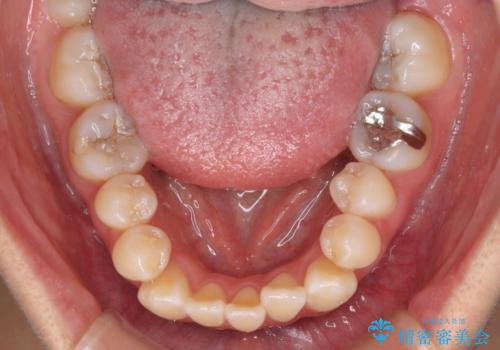

外に飛び出して磨きにくい奥歯と上下前歯の隙間 インビザラインによる矯正治療

- 上下前歯の隙間と、外側を向いていて歯磨きのしにくい奥歯を気にして来院された患者様です。

下顎前歯が1本欠損しており、上下アーチはアンバランスとなりますが、インビザラインを用いて上下の隙間を改善しながら歯列を整えることとしました。

外側を向いている奥歯は、内側にアンカースクリューを埋入して牽引の固定ゲント氏、部分的にワイヤー装置を用いることで歯列に納めることとしました。

下顎前歯の1本欠損により左右の咬合が不安定となり、治療経過で噛みにくい状態が続きましたが、最終的には違和感なく噛めるようになりました。